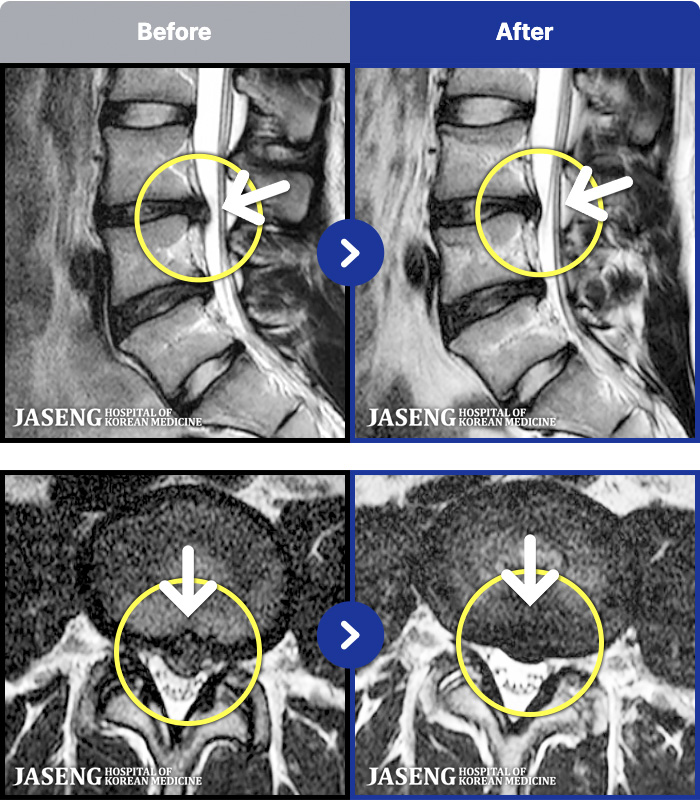

MRI ġ

1,237 MRI ũ ʸ Ȯϼ.